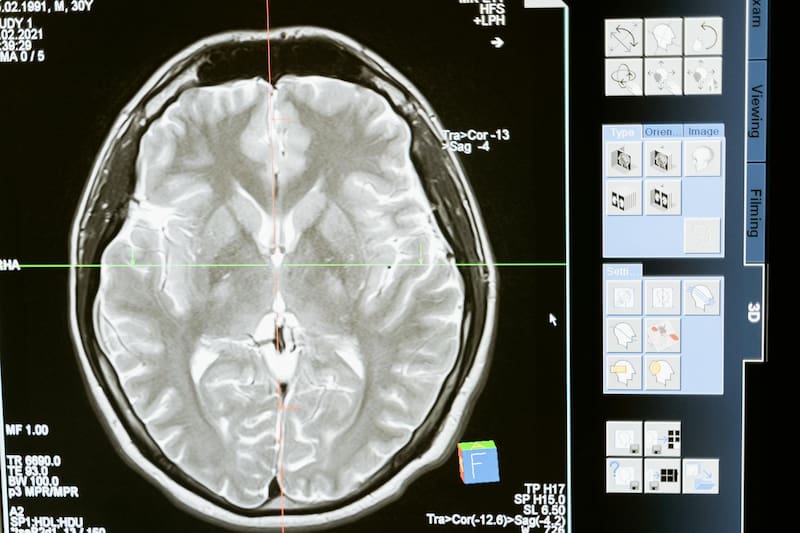

Contra todo pronóstico, un niño de 13 años venció uno de los cánceres más letales que existen. Se trata de un glioma en el tronco cerebral que es inoperable y que suele tratarse con radioterapia para intentar frenar su avance.

Lucas empezó a responder positivamente. “A lo largo de las IRM, vi el tumor desaparecer completamente”, relató el pediatra. Pese a los resultados positivos, temía que al dejar el medicamento el cáncer volviera, por lo que prefirió que el niño continuara con el tratamiento, no obstante, Lucas dejó de tomar los medicamentos un año y medio antes.

“No conozco en el mundo ningún caso como el suyo”, aseguró Grill. Y es que el tumor de Lucas presentó una mutación “extremadamente rara” que, según suponen, habría hecho que las células tumorales sean más sensibles al medicamento, logrando así erradicar el cáncer completamente.